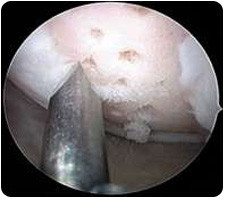

Mikrofrakturierung:

Im Rahmen einer Gelenkspiegelung (Arthroskopie) wird der unter dem Knorpel liegende Knochen mit speziellen Ahlen oder Bohrern eröffnet. Das Blut, das den Defekt füllt, enthält körpereigene Reparaturzellen (sog. Stammzellen). Nach ca. 6 Wochen ist die Defektzone mit Knorpelersatzgewebe ausgefüllt. Zur Sicherung des OP-Erfolges ist eine Teilbelastung des operierten Beines für einen Zeitraum von 6 Wochen erforderlich.